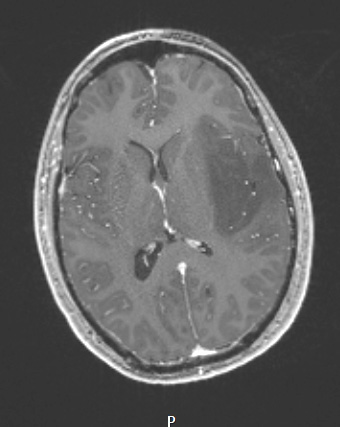

A T1-weighted scan shows a hypointense mass which fails to enhance with contrast.